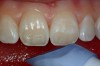

After the preparation is etched with 37% phosphoric acid for 15 seconds (Figure 4), the etchant is vigorously rinsed off for at least another 15 seconds or more. The preparation is then thoroughly dried (enamel and dentin), then the dentin is rewetted with a desensitizer (AquaSeal B™: AcquaMed Technologies, Chicago, IL; Gluma®, Heraeus Kulzer, Armonk, NY) (Figure 5) and high-volume suction is placed within a millimeter of the prepared surfaces for 2 seconds (Figure 6), and then removed. This will create a perfect, moist surface to place a hydrophilic primer, not too desiccated (collapsed collagen), and not too moist.7 A fifth-generation dentin bonding adhesive (OptiBond® Solo Plus™: Kerr Corporation, Orange, CA; Adper™ SingleBond, 3M ESPE, St. Paul, MN; Prime & Bond® NT™, DENTSPLY International, York, PA) is copiously placed with a microapplicator and agitated into the prepared surface (Figure 7). After air-thinning and evaporation of the solvent (ethanol), the adhesive is light-cured according to the manufacturer’s instructions. Figure 8 shows the completed restoration of the facial surfaces of tooth Nos. 8 and 9 (Herculite® Ultra: Kerr Corporation; Kalore™, GC America, Alsip, IL; Esthet-X® HD: DENTSPLY International; Amaris®, VOCO America, New York, NY; Rok, SDI).

Figure 4  The preparations are etched for 15 seconds using 37% phosphoric acid then rinsed with air-water spray for an additional 15 to 20 seconds.

Figure 4

Figure 5  After air-drying the tooth surface, it is rewetted with a desensitizer to help seal the dentinal tubules with HEMA and fluoride before the application of the bonding agent.

Figure 5

Figure 6  A two-second placement of the high-volume suction within a few millimeters of the prepared surface creates an optimally wetted dentinal surface for the application of bonding resin.

Figure 6

Figure 7  The prepared enamel and  dentin is saturated with bonding resin.

Figure 7

Figure 8  Completed direct composite restorations on tooth Nos. 8 and 9.

Figure 8